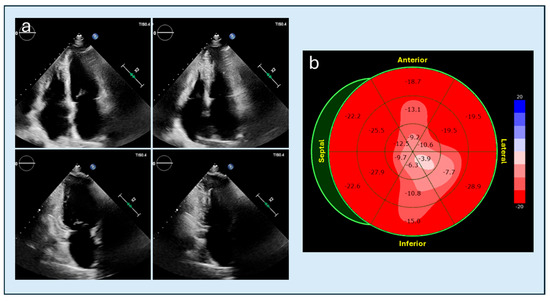

The use of non-invasive imaging techniques is undeniably one of the aspects that best characterize modern cardiology. With the implementation of percutaneous interventional procedures in the treatment of structural heart disease, and current advances in the management of chronic ischemic heart disease, metabolic storage diseases, and heart failure in clinical practice, imaging methods are required to provide increasingly sophisticated evaluation parameters, in order to adopt adequate therapeutic strategies and identify the patients best suited to undergo certain procedures. Therefore, clinicians in cardiac patient management cannot ignore the power of the complete and precise information provided by non-invasive diagnostic methods such as echocardiography, cardiac magnetic resonance imaging, cardiac CT, and nuclear cardiology, which can greatly facilitate correct diagnosis and adequate prognostic stratification.